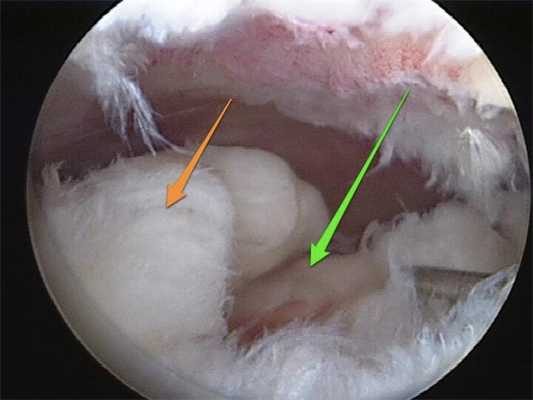

1. Диагностическая артроскопия проводится для оценки выраженности внутрисуставных изменений и подготовки внутрисуставных структур для запланированного вмешательства, например, в случаях, когда после предшествующей артроскопии или другой диагностики коленного сустава уже прошло достаточно много времени

2. В ходе диагностической артроскопии подтверждается наличие дефицита (или недостаточности мениска) после выполненной ранее субтотальной или тотальной менискэктомии, оценивается выраженность вторичных хондральных изменений, которые также могут потребовать лечения, особенно в случаях, когда первичное вмешательство на коленном суставе выполнялось в другом учреждении или другим хирургом (рис. 3).